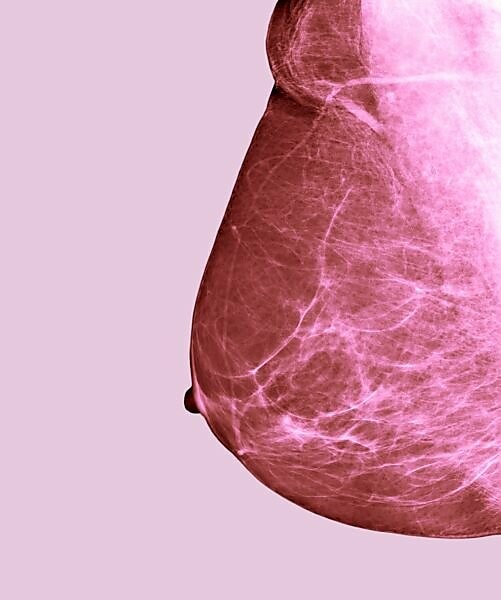

How Old For Mammogram - What age recommended age for a mammogram?. Clinicians should discuss whether to screen for breast cancer with mammography before age 50 years. We will call you within one business day to confirm. And there is insufficient evidence, the task force said at the time, to accurately assess. Nov 18, 2018 · "rather than a blanket statement that everyone over age 75 should get a mammogram, many guidelines recommend that if the woman has a life expectancy of at least five years and is in good general. However, for women with genetic mutations, screening can begin at 25, and in women with a family history of breast cancer, screening is often initiated 10 years earlier than the first affected relative in the family.

In general, screening mammograms are not recommended for women under 40 years old. Your 360° oncology resource for the latest updates and news in breast cancer However, for women with genetic mutations, screening can begin at 25, and in women with a family history of breast cancer, screening is often initiated 10 years earlier than the first affected relative in the family. Saturday appointments available at most locations. What age should women stop getting mammograms? Clinicians should discuss whether to screen for breast cancer with mammography before age 50 years. 10 best exercises for start after breast cancer diagnosis. Mayo clinic supports screening beginning at age 40 because screening mammograms can detect breast abnormalities early in women in their 40s.

What age recommended age for a mammogram? Your 360° oncology resource for the latest updates and news in breast cancer Top exercises for breast cancer and breast health. Complete our online form to schedule a mammogram in the texas medical center, league city, the woodlands or west houston diagnostic imaging. Preventive services task force (uspstf) guidelines recommend a mammogram every two years for women ages 50 to 75 with an average risk of developing breast cancer. Mayo clinic supports screening beginning at age 40 because screening mammograms can detect breast abnormalities early in women in their 40s. May 01, 2017 · the current u.s. Nov 18, 2018 · "rather than a blanket statement that everyone over age 75 should get a mammogram, many guidelines recommend that if the woman has a life expectancy of at least five years and is in good general. Findings from randomized trials of women in their 40s and 50s have demonstrated that screening mammograms decrease breast cancer deaths by 15 to 29 percent. We will call you within one business day to confirm. How old do i have to be to get a mammogram? For older women, the uspstf said there isn't enough evidence of the potential risks and benefits of mammography on which to base a recommendation. Saturday appointments available at most locations.

Findings from randomized trials of women in their 40s and 50s have demonstrated that screening mammograms decrease breast cancer deaths by 15 to 29 percent. However, for women with genetic mutations, screening can begin at 25, and in women with a family history of breast cancer, screening is often initiated 10 years earlier than the first affected relative in the family. And there is insufficient evidence, the task force said at the time, to accurately assess. Discussion should include the potential benefits and harms and a woman's preferences. How often should women of age have a mammogram?